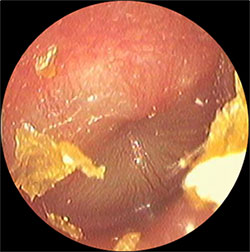

・鼓膜の発赤を認める

・鼓膜の内側には白色の膿がみられる

などの症状がでてきます。